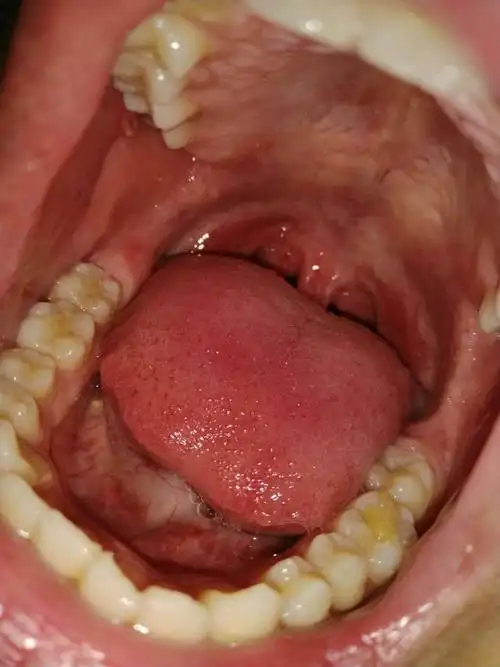

图片扁桃体脓肿图片扁桃体周围脓肿图片口腔肿瘤切除图片肺肿瘤切除图

我的口腔正常么?还有突出的是什么,感觉是

谁能帮我看一下我的口腔和咽喉

口腔科 请进 为什么这里疼? 有图片

我得口腔怎么治疗,如图请请指教 现在症状是喉咙不舒服,肺呼吸有点疼